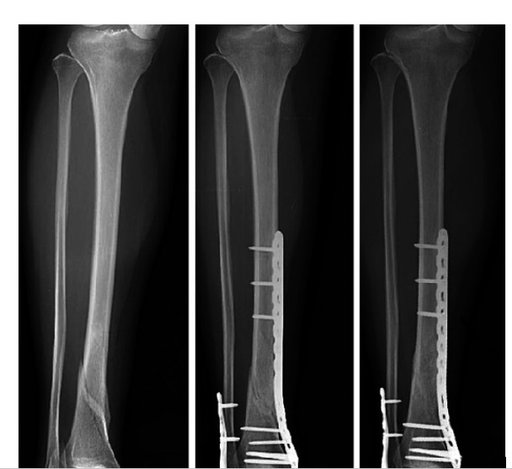

При лікуванні переломів гомілки індивідуально для кожного хворого підбирається найкращий метод фіксації з використанням , як блокуючих інтрамедулярних систем, так і накістковим остеосинтезом з використанням малоінвазивної техніки операції.